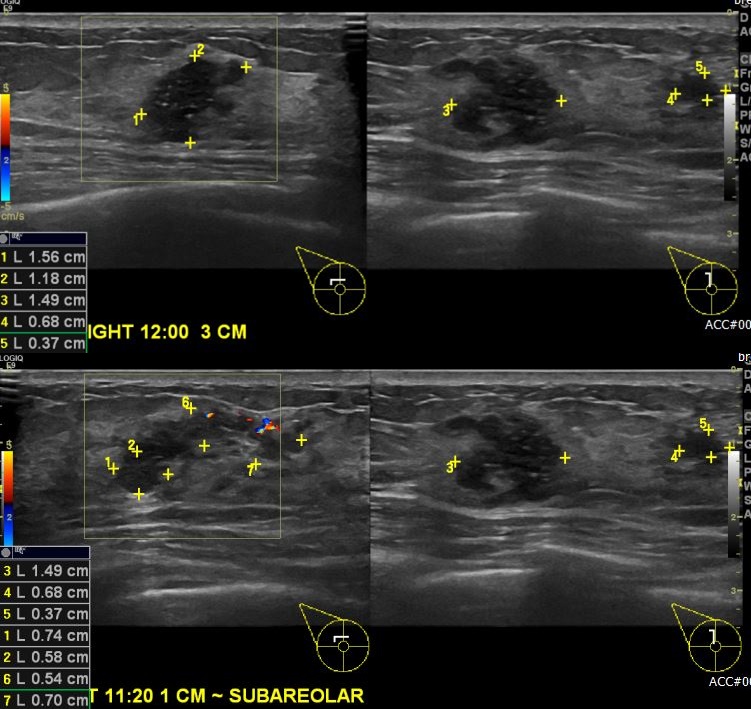

상기환자 우측 만져지는 멍울로 내원하신 40대 여성분으로 본원 초음파 시행후 우측 12시 방향 3cm 떨어진 거리의 멍울과, 11시 유두 밑 부위 각가 조직검사 시행하여  각각  우측

유관암 진단 되었습니다.